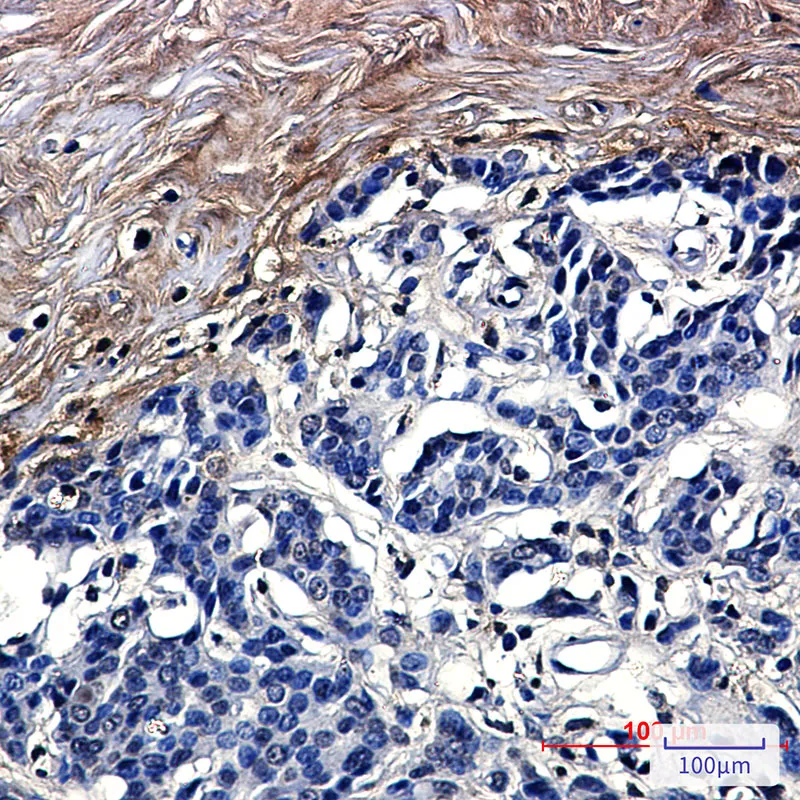

SOX9 Rabbit Monoclonal Antibody

Cat: AMRe01534

Size1:50μl Price1:$158

Size2:100μl Price2:$288

Size3:500μl Price3:$1200

Size2:100μl Price2:$288

Size3:500μl Price3:$1200